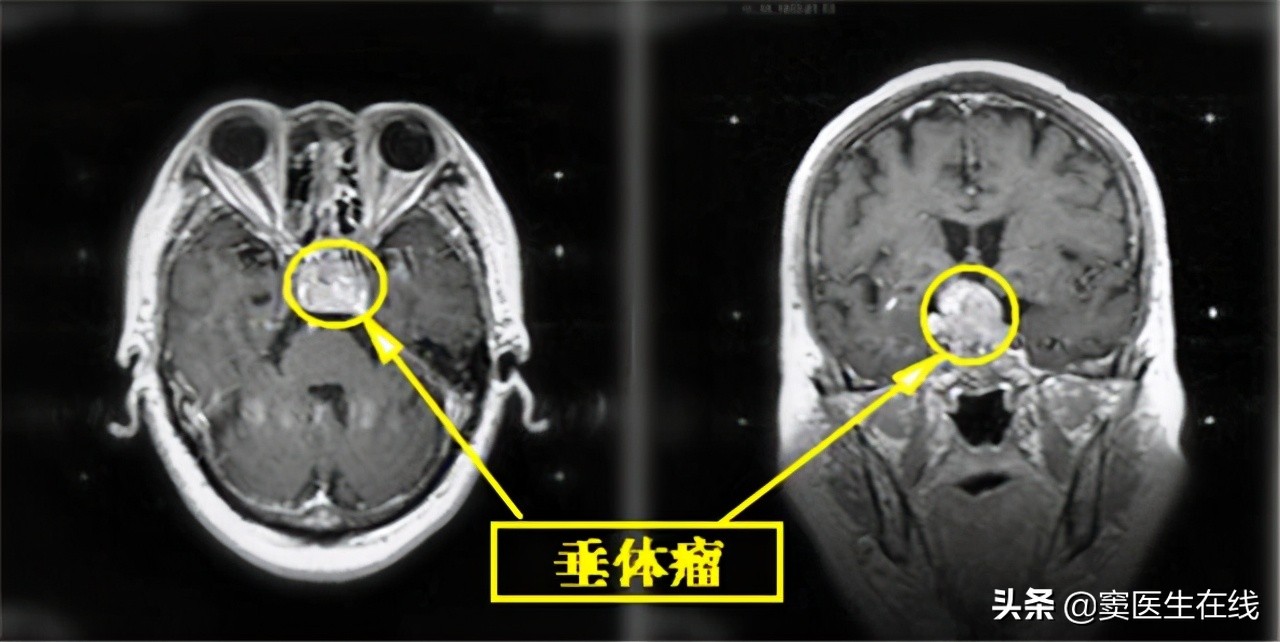

●高泌乳素瘤

若检查发现瘤体小可采用该药物作用保守药物治疗服用,能够 帮助抑制在术前抑制瘤体增长 , 让手术切除更加顺利,也可以作为术后药物以继续降低高泌乳素水平依旧增高。

●治疗 垂体大腺瘤患者 时,或许会导致脑脊液异常漏出的可能。

因为孕期内孕妇的激素水平属于不断波动的状态,因此为了控制激素增长水平,应在孕期内 定期观察瘤体变化情况 ,避免诱发不良事件的发生。

对于患有垂体微腺瘤孕妇、高泌乳素血症孕妇,若胎儿发育正常,若孕妇出现视野缺损,或者能够清晰判断瘤体在孕期内无继续发展的可能,若没有不适应症状的表现,那么则应继续服用甲磺酸溴隐亭。 但是也有部分患者可能会出现停用该药物后,发生瘤体增大的可能,因此需经过医生结合临床变现以及检查报告数值来判定是否给予停药。